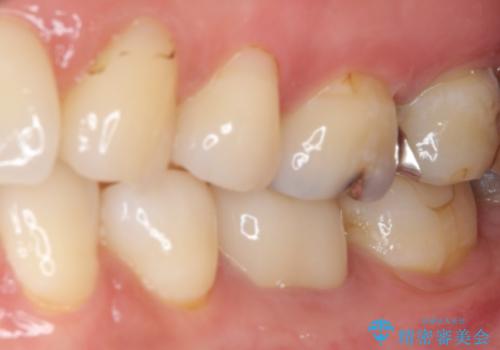

- 口を開けたときに目立ってしまう銀歯をセラミックに替えたいとのことで来院された患者様です。

上顎や親知らずにも銀歯がありましたが、今回の治療では目立つ下顎の銀歯4歯をセラミッククラウンやセラミックインレーに置き換えることにしました。

話をする度に相手の視線が銀歯に注がれている気がしているとのことでしたが、目立つ銀歯を自然な色合いに仕上げることができ、患者様には大変満足していただきました。